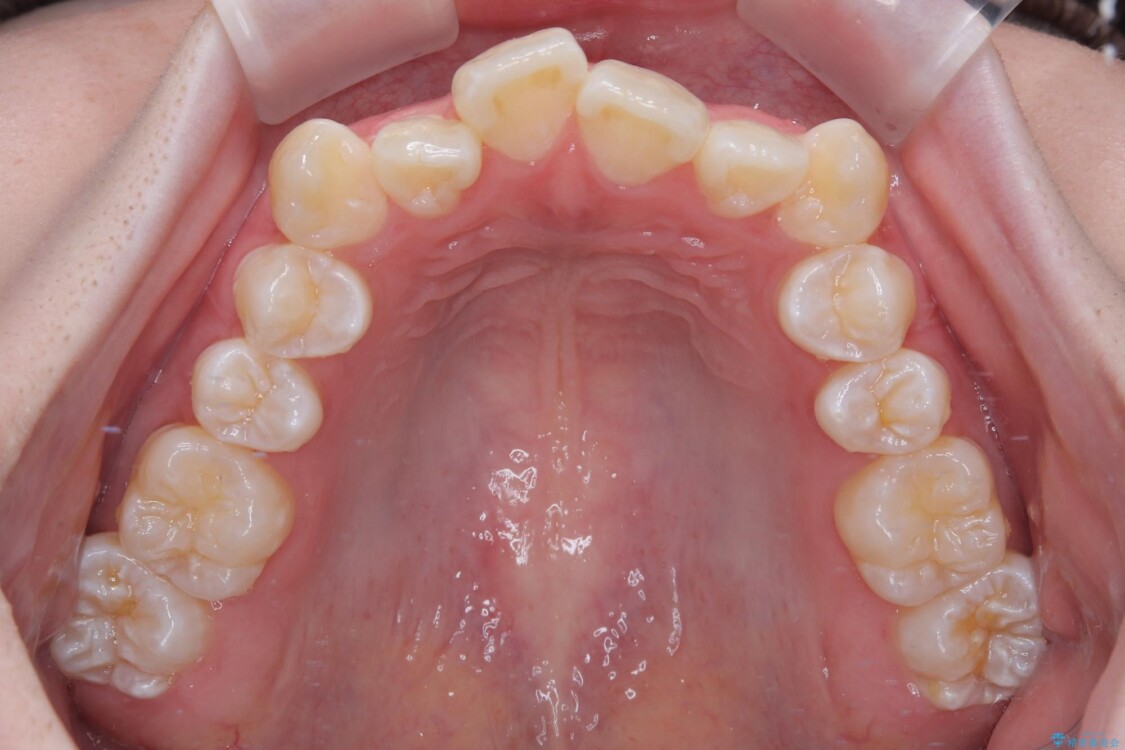

治療前

• 【モニター】前歯のデコボコをスッキリ解消!目立ちにくいワイヤー矯正でスピーディに治療完了 治療前画像

「前歯のデコボコ(叢生)をきれいに整えたい」とのことでご来院されました。